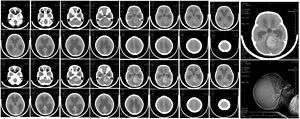

| CT scan, showing a tumorous mass in the posterior fossa, giving rise to obstructive hydrocephalus, in a six-year-old girl | |

The tumor is distinctive on T1 and T2-weighted MRI with heterogeneous enhancement and typical location adjacent to and extension into the fourth ventricle.